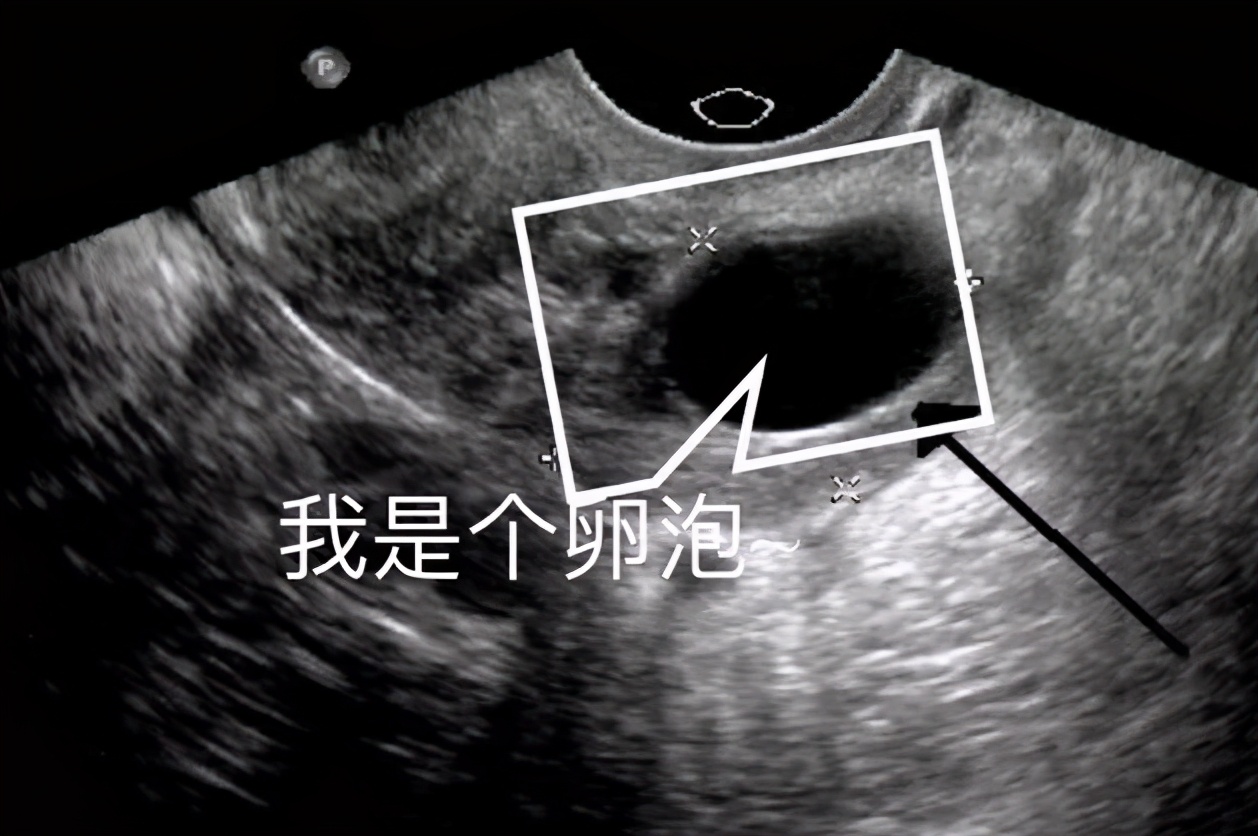

囊肿大多可以通过超声发现(其实CT、磁共振都可以诊断囊肿,但在妇产科都不如超声实用)。在超声画面中,液体是呈黑色的,所以看超声时,液囊就是个黑色的圆,如下图。

囊肿里所含的液体稀薄清亮时,在超声下就是个黑窟窿,又经常在口头上被称作“液囊”。

这和我们心心念念的卵泡长得很像啊,确实,卵泡就是个含着液体的泡,也算的上是广义上的“液囊”。